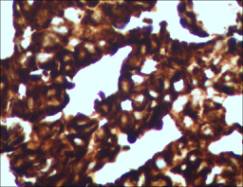

图示:腹水沉渣包埋发现腺癌细胞团TTF-1灶+,ALK融合蛋白阳性

病理活检(B1513618)示:(子宫内膜)形态及免疫组化符合:低分化腺癌伴局灶性鳞状分化,免疫组化TTF-1+、NapsinA+提示:肺癌转移而来。免疫组化:CK+,Vim-,P63灶+,CK5/6灶+,CK7+,CK18,CEA+,CA125+,Ki-67+80%,TTF-1+,NapsinA+,ER-,PR-,P53+70%。

查子宫内膜癌ALK融合蛋白阳性,ALK基因检测亦为阳性;

为明确腹水来源,根据免疫组化,考虑肺来源可能,但不能完全排除子宫内膜来源,再查腹水沉渣ALK融合蛋白为阳性,则支持肺来源的证据更多一些。